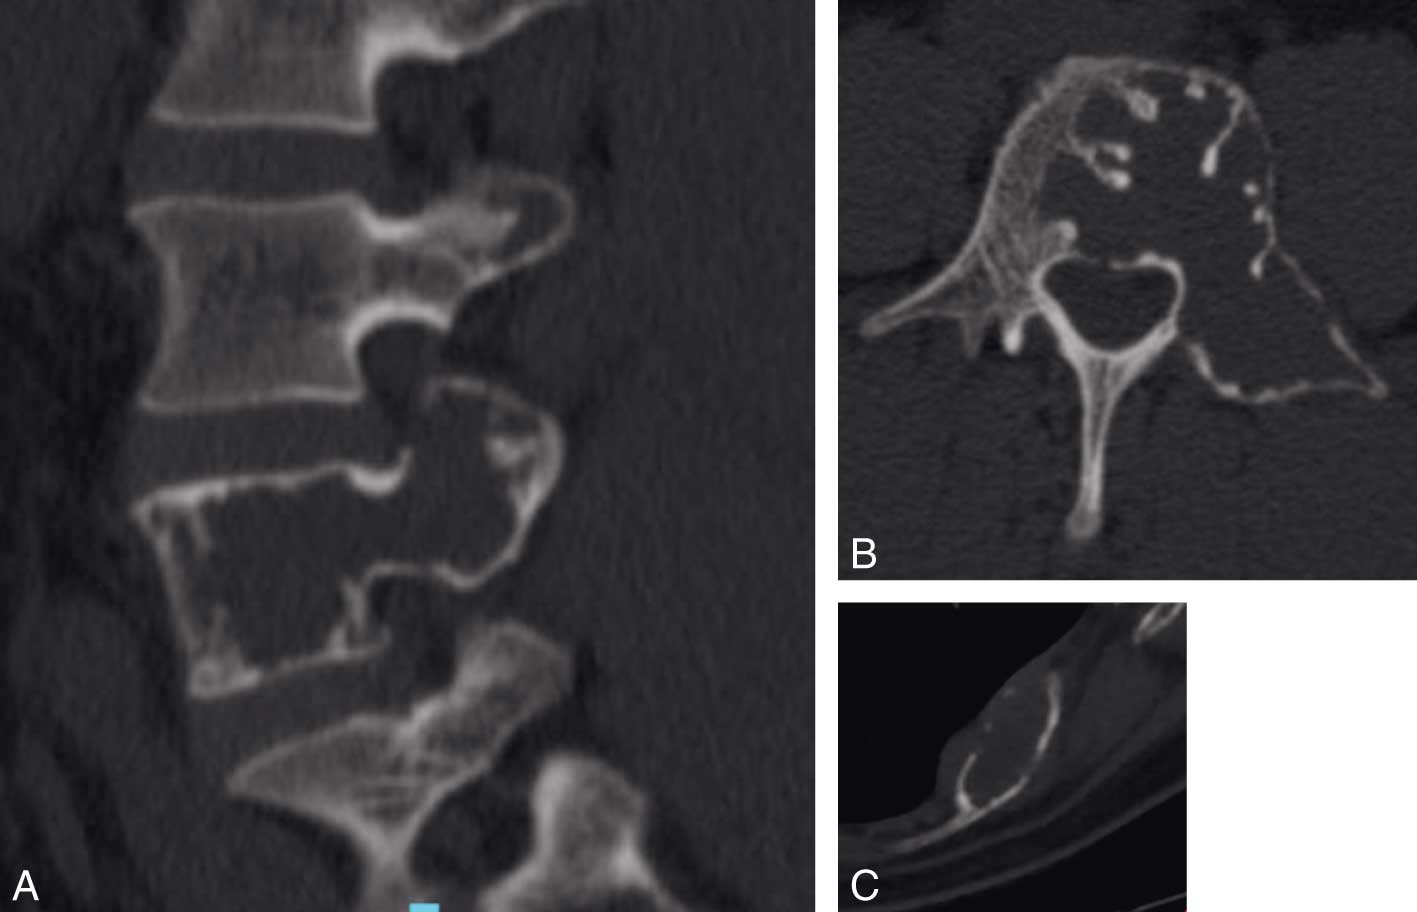

Les tumeurs malignes, les plus frequentes, souvent caracterisees par une rupture de la corticale, une extension periosseuse et des limites floues sont dominees par les metastases, le myelome multiple et les chondrosarcomes Les tumeurs benignes respectent le plus souvent la corticale et presentent des limites nettes. Une tumeur osseuse bénigne est une masse non cancéreuse qui ne se propage pas à d'autres parties du corps (ne forme pas de métastases) et qui ne met habituellement pas la vie en danger Les tumeurs osseuses bénignes sont assez courantes, mais on ne connaît pas la cause de la plupart des types. Ces tumeurs et pseudotumeurs peuvent être de nature fibreuse, cartilagineuse, osseuse, kystique, graisseuse, vasculaire et notochordale Une connaissance précise du contexte clinique du patient est un prérequis indispensable.

Connaître les principales tumeurs osseuses primitives bénignes et malignes En présence d'un patient souffrant de métastase(s) osseuse(s) révélatrice(s), savoir orienter l'enquête étiologique en fonction du terrain, des signes cliniques et biologiques, du nombre et de l'aspect des métastases. Ce cours est déstiné aux residents de premiere année des études médicales spécialisées en imagerie médicale , conformément au programme d'Alger. Je suis quoi Les métastases osseuses sont une complication fréquente des tumeurs malignes avancées Après les poumons et le foie, les os sont l’un des sites métastatiques les plus courants pour la plupart des néoplasmes Les métastases osseuses peuvent se produire dans n’importe quelle partie du squelette, mais touchent le plus souvent le bassin, la colonne vertébrale, le crâne.